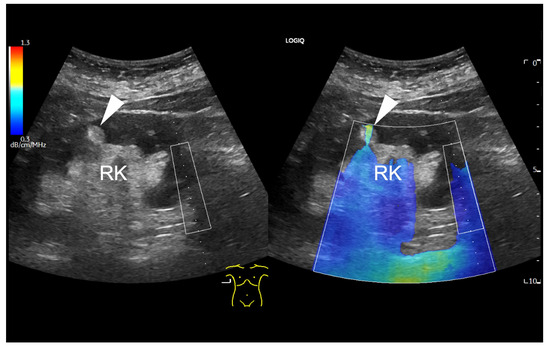

Findings in which the measurement was influenced by given factors, findings without the possibility of a measurement, and findings with no possible measurement but with a positive, fat-rich visual finding in the colour map were recorded in the database separately. An example of a focal renal lesion that was not accessible for UGAP measurement is shown in Figure 2.

Figure 2.

B-mode ultrasound of the right kidney (RK), displaying a focal hyperechogenic lesion (arrowhead) in the cortex, which is barely included in the colour coded attenuation map. The ROI box on the right side of the map can be only moved horizontally due to methodological reasons. Due to the superficial localization of the small renal lesion, the attenuation colour map is only partial applicable (arrowhead).